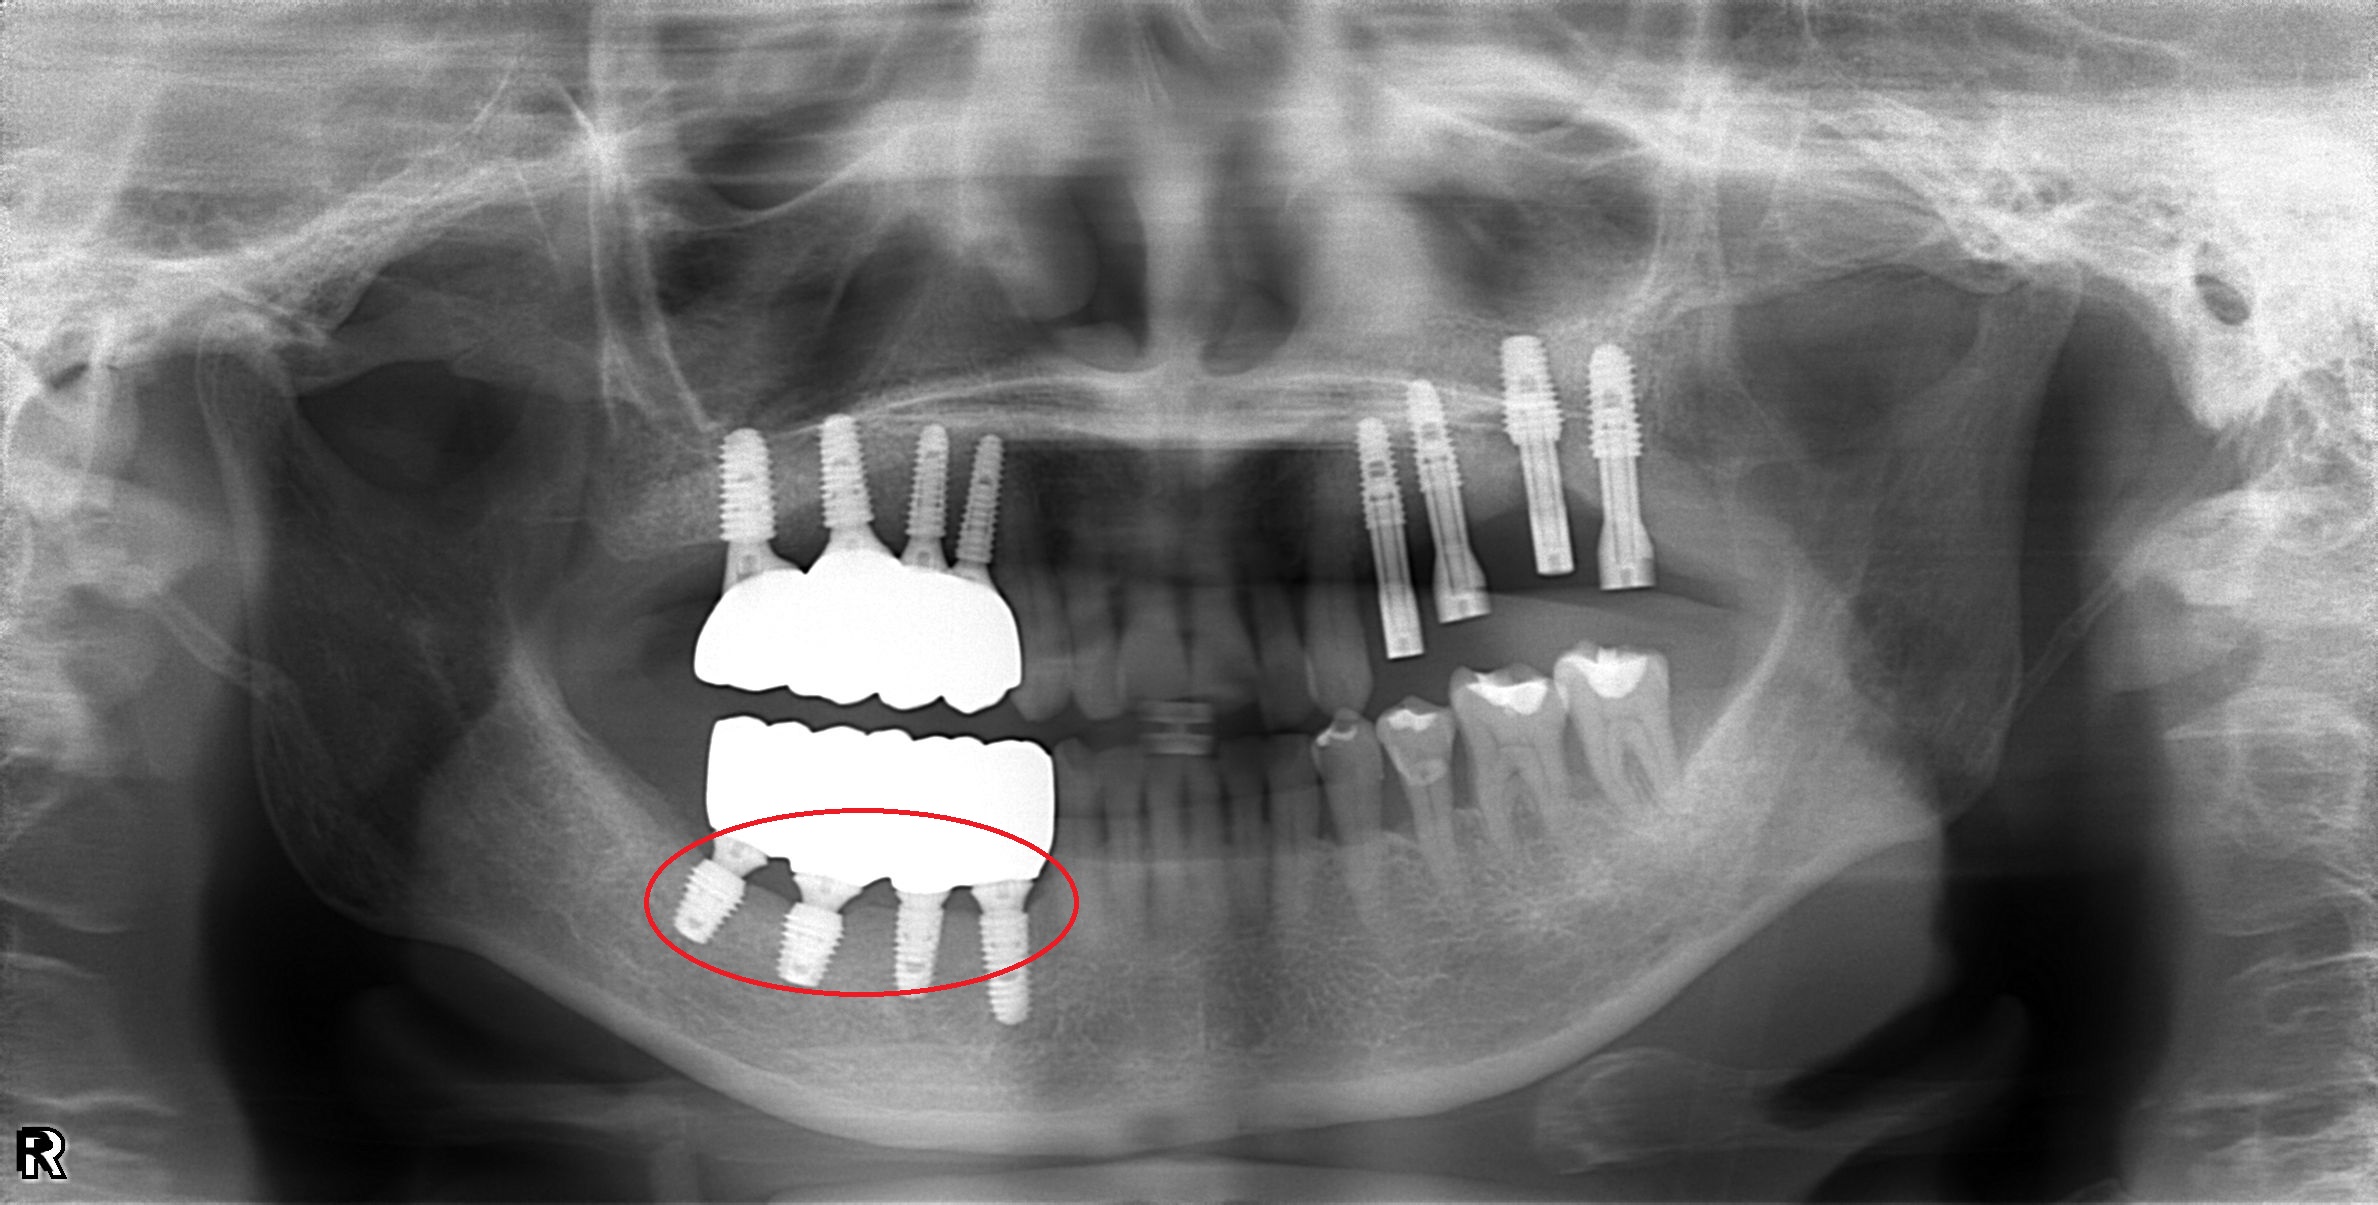

植體周圍炎處理

案例二